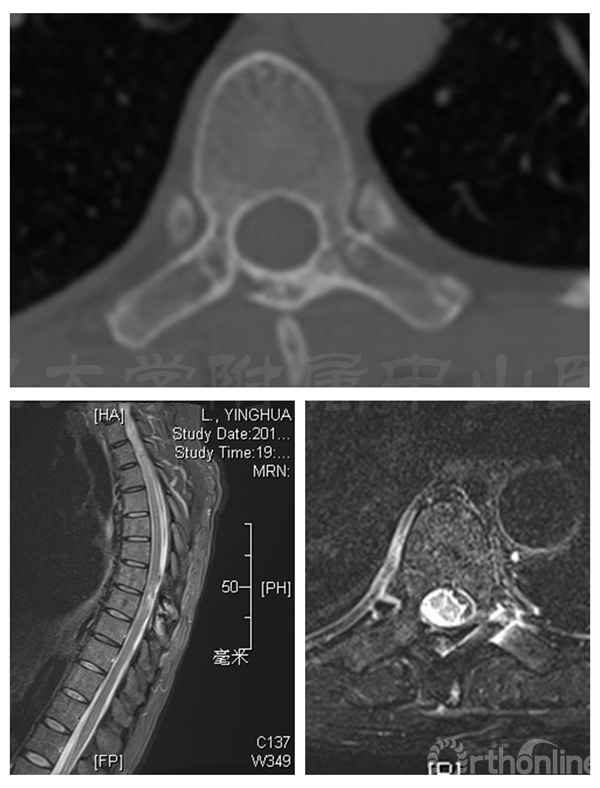

术前三维CT:T7/8水平可见椎管内占位

术前MRI:T7-8水平椎管内占位伴脊髓变性,脊膜瘤可能的大

术后三个月患者腰背痛完全缓解,肌力已恢复至5级,下肢麻木感消失。CT显示:椎板截骨面已骨性愈合,无移位,椎管容积与术前无明显差异

术后半年CT显示两侧椎板截骨面均已骨性愈合,椎管体积无减少。MRI显示椎管内脊膜瘤无复发